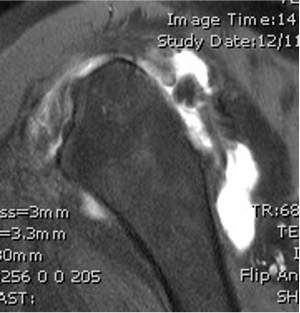

MRI

Rotator cuff tears

MRI with massive supraspinatus tear, subscapularis tear, and large Hill Sachs lesion